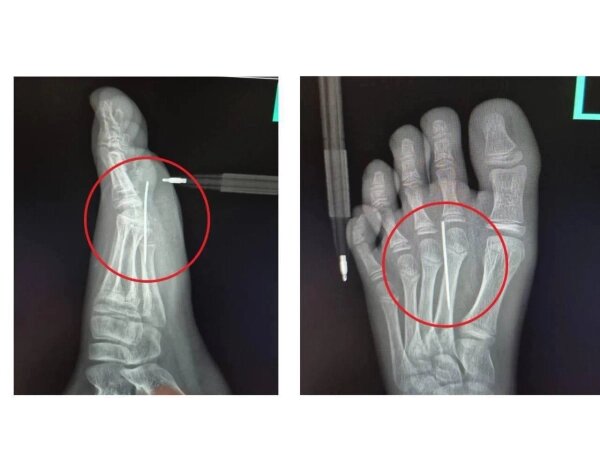

10-летний мальчик получил травму стопы, вырезая печенье из «Игры в кальмара». Ребёнок наступил на иглу и был госпитализирован в Детский клинический центр имени Л. М. Рошаля.

Заведующий травматологическим пунктом Артём Лисенков рассказал, что в больнице врачи сделали рентген, который подтвердил наличие инородного тела в стопе. Иглу аккуратно достали специальным инструментом «Москит». Процедура заняла не больше 3 минут и прошла успешно. Спустя несколько часов пациента уже выписали домой.